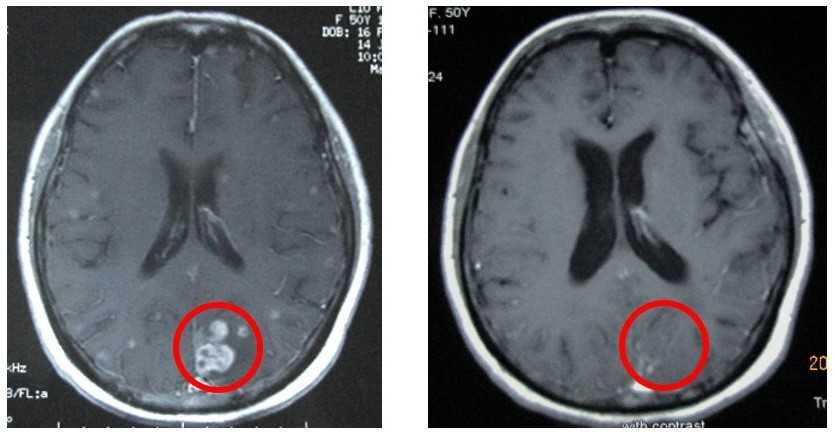

- Лучевая терапия. Применяется как паллиативный метод для локального контроля размеров опухоли, при выраженном болевом синдроме, для уменьшения размеров метастазов (наиболее часто применяется облучение головного мозга).

Метастазы мелкоклеточного рака легкого в мозг: до и после лечения (Китай)

Самыми опасными являются метастазы в головной мозг. Локализация вторичной опухоли в области центров регуляции жизненно важных функций организма приводит к неизбежной смерти.

Метастазы других локализаций также ускоряют наступление летального исхода тем, что нарушают функции органов, вызывают сильные боли. Особенно это присуще метастазам мелкоклеточного рака.

Симптомы, сопровождающие метастазирование онкопроцесса, напрямую зависят от его локализации. При переносе с током крови раковых клеток в головной мозг, пациента будут беспокоить приступы эпилепсии, судорог, расстройство зрительной, двигательной деятельности.